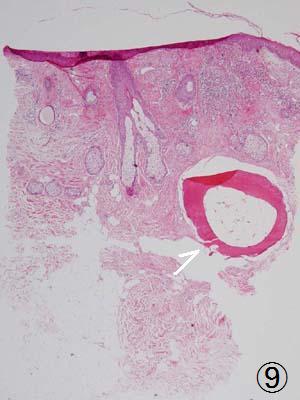

皮膚骨腫

H皮膚の中に形成された骨の組織(矢印)。顔のにきびあとなどに多発して砂粒のようにパラパラ触れる稀な疾患。